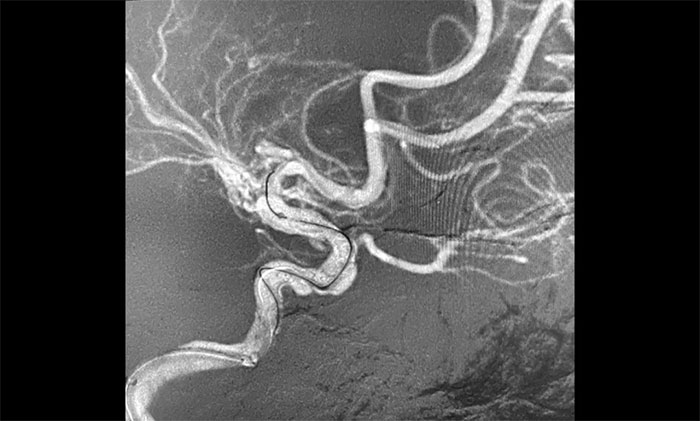

接下来,左颈内动脉海绵窦段、床突段多发动脉瘤处理极具挑战。由于C5、C6、C7段血管极度迂回曲折,类似“N”形,从C4、C5到C6之间的血管约成45°锐角,从C6至C7之间又是约30°锐角,可谓“山路十八弯”,而导丝又是极软,每向前推进一毫米,都非常艰难。这种介入手术对术者的技术要求非常高,如果支架贴合不好,打开不良,还需要用导丝蠕动“按摩”,让支架重新回到血管壁上。

▲ 血管极度迂曲,为手术带来挑战